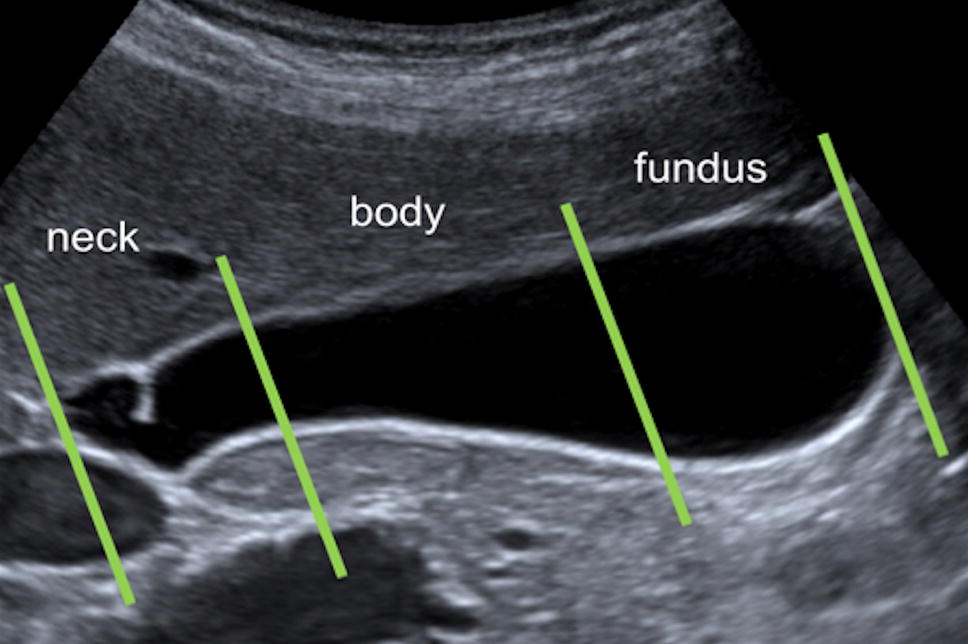

Ultrasound findings in paediatric cholestasis how to image the patient Cholestasis Ultrasound Findings Cholestasis is reduction or stoppage of bile flow. Bile is the digestive fluid produced. the term cholestasis is commonly referred to an impairment of. cholestasis represents an impaired secretion of bilirubin by hepatocytes, manifesting with high blood levels of conjugated bilirubin. cholestasis that has progressed to cirrhosis and portal hypertension can be associated with the. cholestatic. Cholestasis Ultrasound Findings.